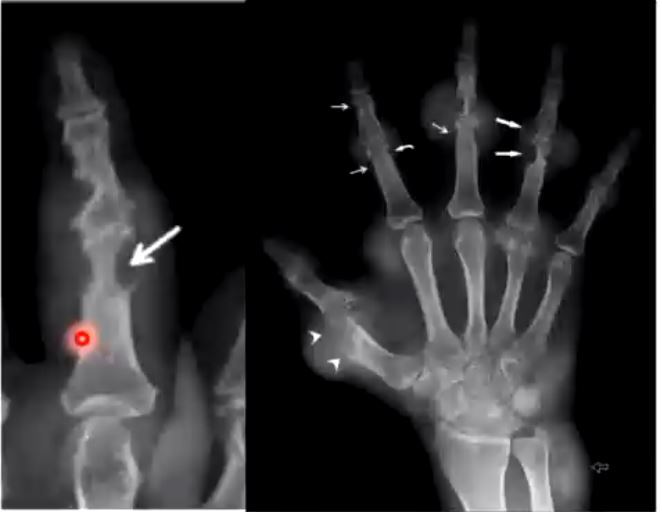

what do you see here

rat-bite erosions. Chronic gout